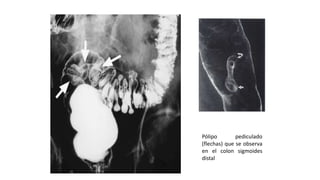

A nivel del

sigmoide

Pólipo pediculado

(flechas) que se observa

en el colon sigmoides

distal